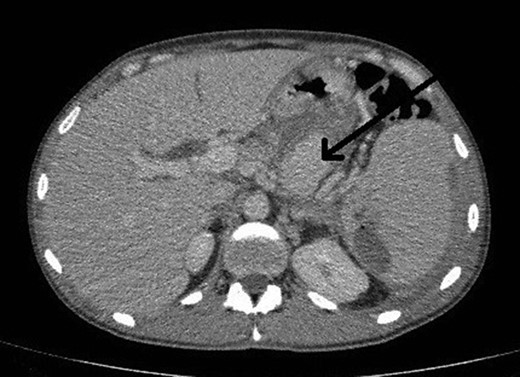

He presented to the local tertiary referral centre complaining of chest pain and the normal ECG, cardiac markers and chest X-ray suggested a non-cardiac cause for the pain. He remained haemodinamically stable and was further investigated with an abdominal ultrasound (USS) and a contrast enhanced computed tomography (CT). The latter demonstrated a 5 × 3.8 cm2 pseudoaneurysm posterior to the stomach and superior to the body of the pancreas but of unclear origin. It also showed a large subcapsular splenic haematoma measuring 10.8 × 7.7 cm2 and a perisplenic collection (Fig. 1).

CT abdomen image shows flow in pseudoaneurysm (arrow) posterior to the stomach and the subcapsular splenic haematoma.